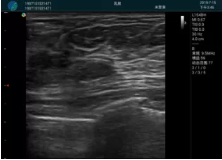

甲狀腺囊性結(jié)節(jié),囊壁鈣化,透聲好

甲狀腺囊性占位